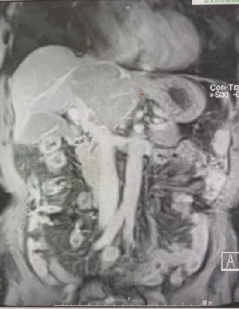

81岁的李阿伯因反复腹痛4个月,且病情持续加重后来金山医院就诊,经检查发现,李阿伯的肝脏尾状叶上长出一个8×6cm的肿物,患肝癌可能性大,突如其来的噩耗让整个家庭措手不及。

术前影像资料

肝脏肿瘤手术属于四级高难度手术,肝尾状叶肿瘤更因其位置较深、毗邻腹腔多个重要大血管、手术空间极为狭小而成为其中最困难、最复杂的一种,被认为是肝脏手术的“禁区”。